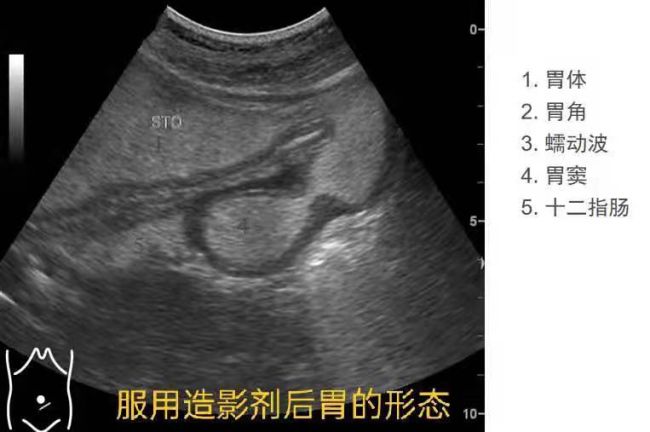

胃,你好吗?——信阳市中心医院成功开展胃超声造影技术

胃角部-体部的j型区域观察10-胃窦11-1胃角前壁11-2胃角后壁12-1胃体